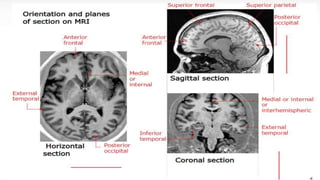

Slicing

7

Sagittal[s-s] Coronal[A-P] Axial[S-I]

Side view Front view Bottom up view

8

9

Imaging planes

10

11